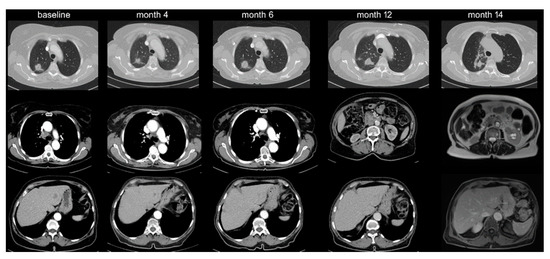

Among IO-monotherapy patients, 38 (13%) showed OPD with decreasing frequency beyond the first line (20% vs. 10%, p < 0.05, Table 1, Figure 1). Furthermore, OPD in patients treated with IO monotherapy in the first line occurred later (after 11 vs. 2 months in median, p < 0.001), involved fewer anatomical sites (mean 1.1 vs. 1.5, p < 0.05), and affected fewer lesions (mean 1.4 vs. 2.3, p < 0.05) compared to OPD in patients receiving IO monotherapy in later lines (Table 2). Lymph nodes (42% of OPD cases, mainly mediastinal, Figure 2 and Table 2) and brain (39%) were affected most frequently, but OPD was also observed in other organs typically affected by NSCLC, namely lung (24%, Figure 3), adrenal glands (16%), bone (8%), liver (5%), skin and soft tissues (3%).

Figure 2. Lymph node oligoprogression. A 66-year-old male patient with adeno-NSCLC (PD-L1 90%) was started on pembrolizumab in November 2017. Nodal progression on the right side was noted in June 2018, which appeared stable in a subsequent restaging in October 2018, even though no change in therapy occurred.

Figure 3. Lung oligoprogression and transitional cell carcinoma of the kidney. A 75-year-old female with adeno-NSCLC (PD-L1 90%) was started on pembrolizumab in September 2017 with response of the primary tumor, mediastinal lymph nodes, and liver metastases. Upon oligoprogression of the primary tumor in March 2018, thoracic radiotherapy was administered. In August 2018, a new kidney lesion was noted that grew oligoprogressive-like. At biopsy, this lesion turned out to be a transitional-cell carcinoma.

The main study population encompassed all 372 stage IV NSCLC patients with radiologically documented disease progression under PD-1/PD-L1 inhibitors among all 636 IO-treated patients in our hospital from March 2013 until September 2019. Treatment consisted of either checkpoint inhibitor monotherapy in various treatment lines (454 IO-monotherapy patients, of which 297 had radiologic evidence of disease progression at the time of study inclusion) or upfront combined chemoimmunotherapy (106 patients, 75 of which with radiologic progression, Figure 1). For analysis, the study population was divided in three groups: patients with IO monotherapy in the first line (n = 89), who were contrasted to patients with IO monotherapy in subsequent treatment lines (n = 208) and to patients with chemoimmunotherapy in the first line (n = 75, Table 1). Imaging studies were performed according to the standard in our institution with chest/abdomen CT and brain MRI scans before treatment start and every 6–12 weeks thereafter (Figure 2). Cases with disease progression suitable for inclusion in this study were identified by a retrospective review of medical records, followed by a review of radiological images in order to characterize the progression pattern as diffuse or OPD. Other clinical parameters were collected from the patients’ records (Table 1). Patients with early death before the first restaging, and patients who died during the stable phase of the disease after the initial response due to other reasons, were non-evaluable and excluded from this analysis (n = 66). Patients with chemoimmunotherapy after pretreatment with tyrosine kinase inhibitors for actionable genetic alterations were also excluded from this study because of potential biologic differences (n = 10, Figure 1). Testing for actionable EGFR/ALK/ROS1/BRAF mutations had been performed as indicated (e.g., in case of adenocarcinomatous histology or never/light-smoker status) for all patients at initial diagnosis, followed by administration of targeted therapies if positive, so that practically no cases with treatable genetic alterations were included in this analysis.